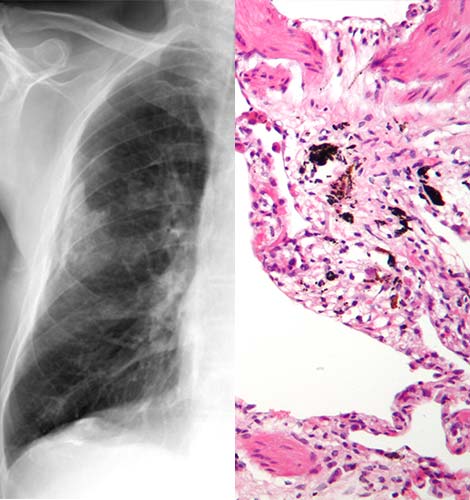

El asbesto nos afecta por la inhalación y su repetida exposición puede causar asbestosis

La asbestosis es una:

- Enfermedad crónica, grave y progresiva de los pulmones.

- La asbestosis no es un cáncer.

- Es una enfermedad que restringe el funcionamiento de los pulmones haciendo más difícil la respiración.

- La asbestosis es provocada por la inhalación de fibras de asbesto.

Con el tiempo, La asbestosis provoca la cicatrización progresiva de los pulmones, por lo que se pierde la elasticidad del tejido pulmonar, lo que puede ser lo suficientemente grave como para causar la muerte o discapacidad.